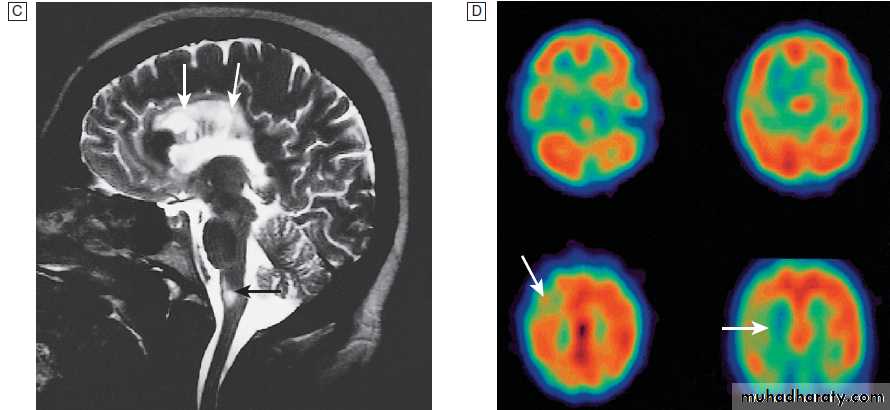

Different techniques of imaging the cervical spine. A Lateral X-ray showing bilateral C6/7 facet dislocation. B Myelogram showing

widening of cervical cord due to astrocytoma (arrows). C MRI showing posterior epidural compression from adenocarcinomatous metastasis to the posterior arch of T1 (arrows).